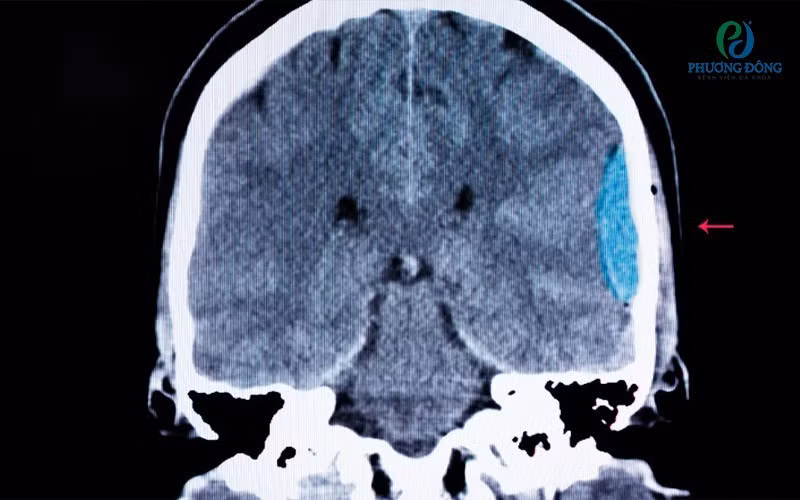

Tuy nhiên, kết quả chẩn đoán hình ảnh cho thấy bệnh nhân bị tụ máu nhu mô não vùng thái dương trái, kèm tràn máu não thất bên trái và não thất III. Trước tình trạng nguy hiểm, bệnh nhân được chỉ định nhập viện cấp cứu, điều trị theo chuyên khoa thần kinh.